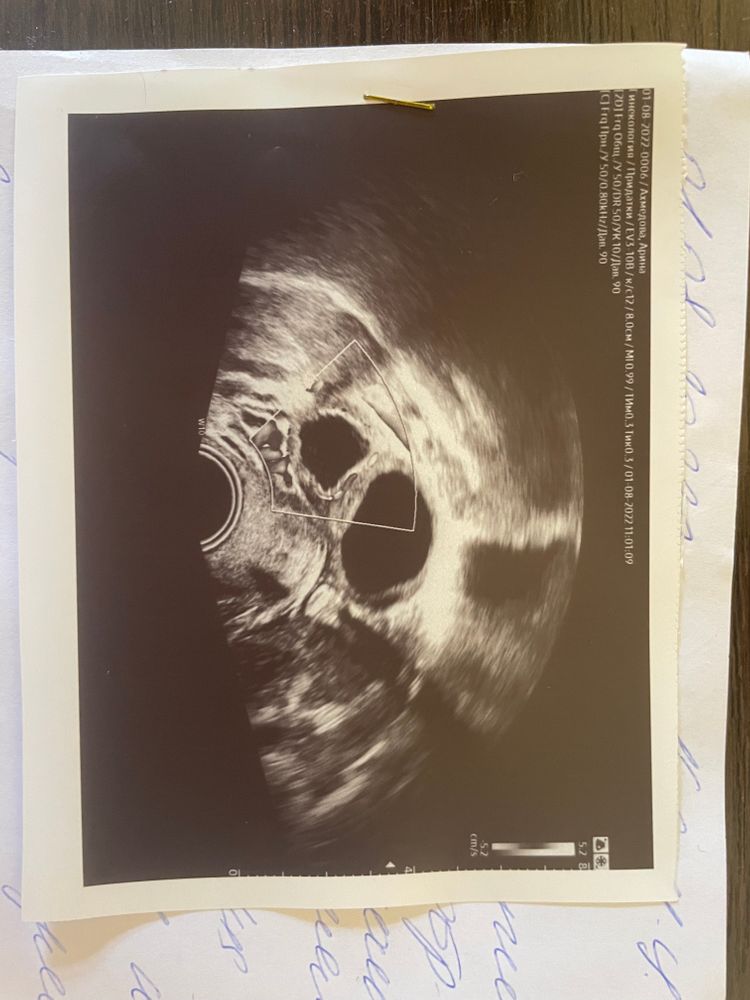

Здравствуйте, прикреплю результат узи

можно ли забеременеть с кистозным жт?

если нет свободной жидкости в заднем своде, значит овуляции не было?

Подскажите, пожалуйста, желтое тело есть или нет? После укола хгч сделала узи на 16д.ц. , узистка ЖТ поставила под вопросом, в заднем своде жидкость есть